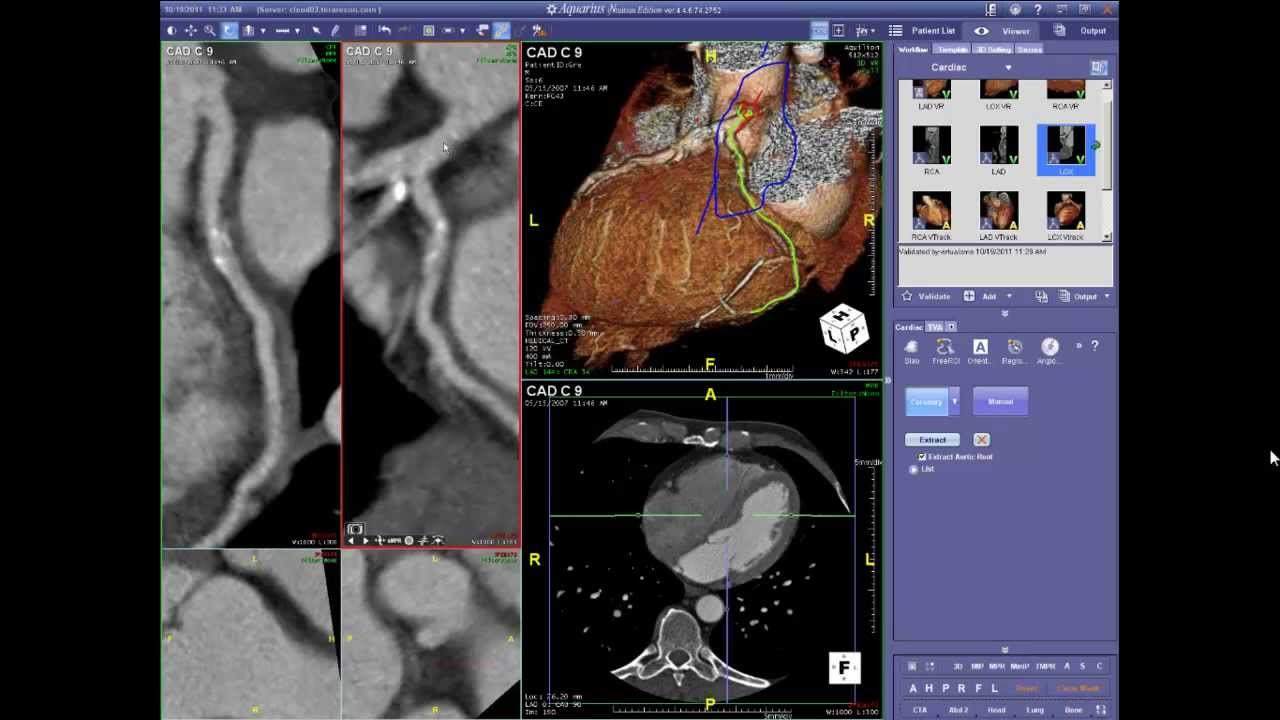

Left Anterior Descending Coronary Artery Anatomy on Coronary CTA

Описание: Detailed review of left anterior descending coronary artery anatomy on cardiac gated coronary CTA.